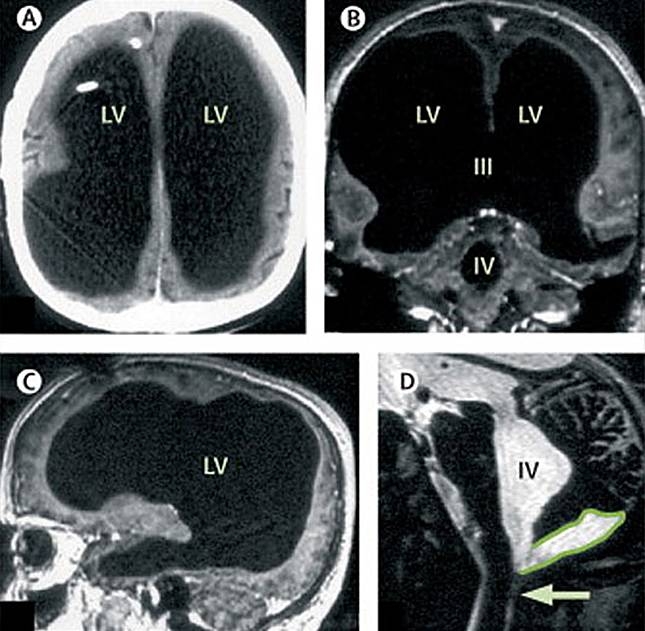

Sau khi quét não cho ông bác sĩ đã đưa ra một kết quả không ngờ, người đàn ông này chỉ có một nửa bộ não so với người bình thường.

Ảnh Xquang cho thấy ông đã mất đi 50-75% bộ não. |

Các bác sĩ đã phát hiện ra nguyên nhân của căn bệnh này có thể do người đàn ông 44 tuổi này đã bị mắc bệnh tràn dịch não sau khi sinh ra hoặc là bị bệnh não nước từ lúc 6 tuổi.

Trong 30 năm qua, chất lỏng dư thừa cứ ngày càng nhiều lên trong đầu người đàn ông này, và dần dần nó thay thế 50-75% bộ não của ông.